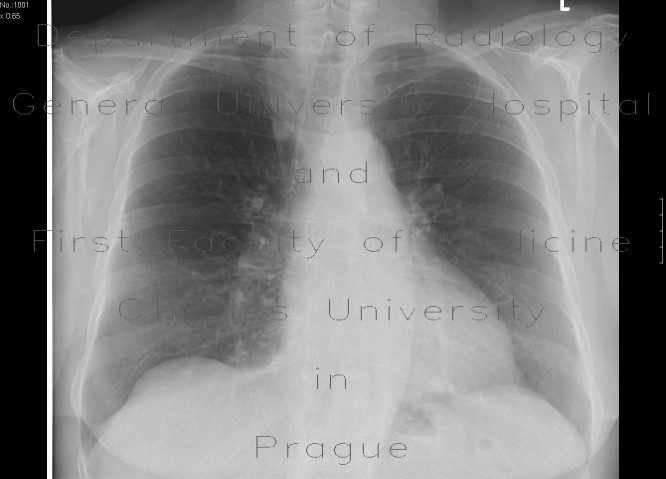

Tumors Of The Paranasal Sinuses - Lieberman's ERadiology